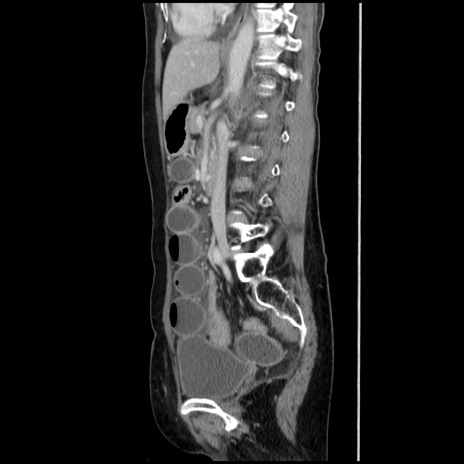

症例32(矢状断像)

【症例】40歳代 女性

【主訴】上腹部痛、嘔気・嘔吐

【現病歴】約9時間前頃から急に上腹部痛、嘔気、嘔吐が出現。改善しないため救急要請。

【既往歴】子宮頚癌(広汎子宮全摘術、放射線療法)、腸閉塞

【身体所見】腹部:平坦、軟、腸雑音亢進、上腹部を中心に腹部全体に圧痛あり。

【データ】WBC 8400、CRP 0.03